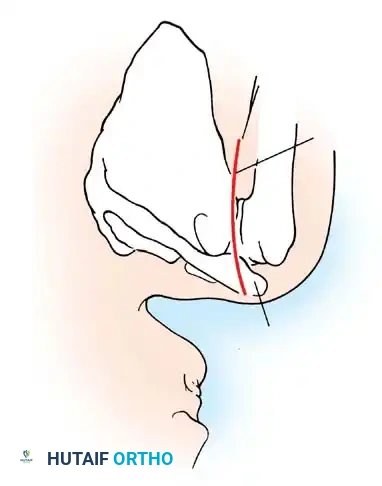

A Hill-Sachs lesion is an impaction fracture of the posterolateral humeral head, created when the head is driven against the hard anterior glenoid rim during dislocation. Burkhart and DeBeer introduced the concept of the "engaging" Hill-Sachs lesion, which levers the humeral head out of the joint when the arm is abducted and externally rotated.

Concurrently, anterior glenoid rim fractures or attritional bone loss can occur. Itoi demonstrated that a 20% loss of the anterior glenoid width critically compromises stability, rendering soft-tissue repairs (like an isolated Bankart repair) biomechanically insufficient. Advanced imaging (3D CT or MRI arthrography) is mandatory to quantify bone loss.